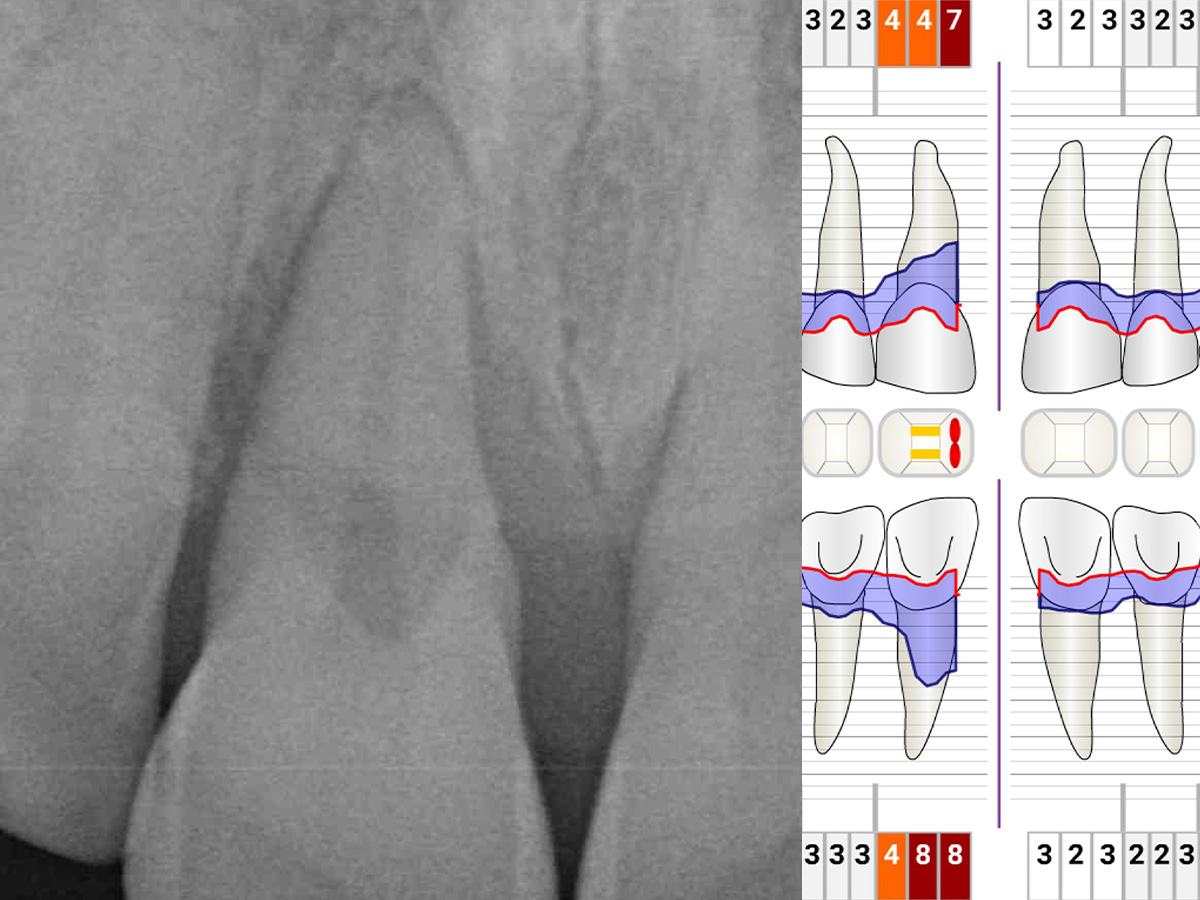

Während der intraoralen Untersuchung wurden eine erhöhte Beweglichkeit sowie erhöhte Taschensondierungstiefen und klinische Entzündungszeichen an Zahn 11 festgestellt. Ein intraorales Röntgenbild wurde angefertigt. Die intraossäre Defektkomponente gemeinsam mit dem hohen Niveau an Mundhygiene bieten eine gute Grundlage für einen regenerativ-parodontalchirurgischen Eingriff. Zehn Tage vor dem Eingriff wurde der Zahn mit dem Nachbarzahn verblockt und ein lokales Antibiotikum in die parodontale Tasche appliziert, um zum Zeitpunkt des Eingriffs möglichst entzündungsarme Verhältnisse vorzufinden. Unmittelbar vor Beginn des chirurgischen Eingriffs wurde der Defektboden mit einer Parodontalsonde ausgelotet, um Informationen über die dreidimensionale Defektmorphologie zu erhalten (Abb. 1-3).

Abbildung 1

Abbildung 2

Abbildung 3